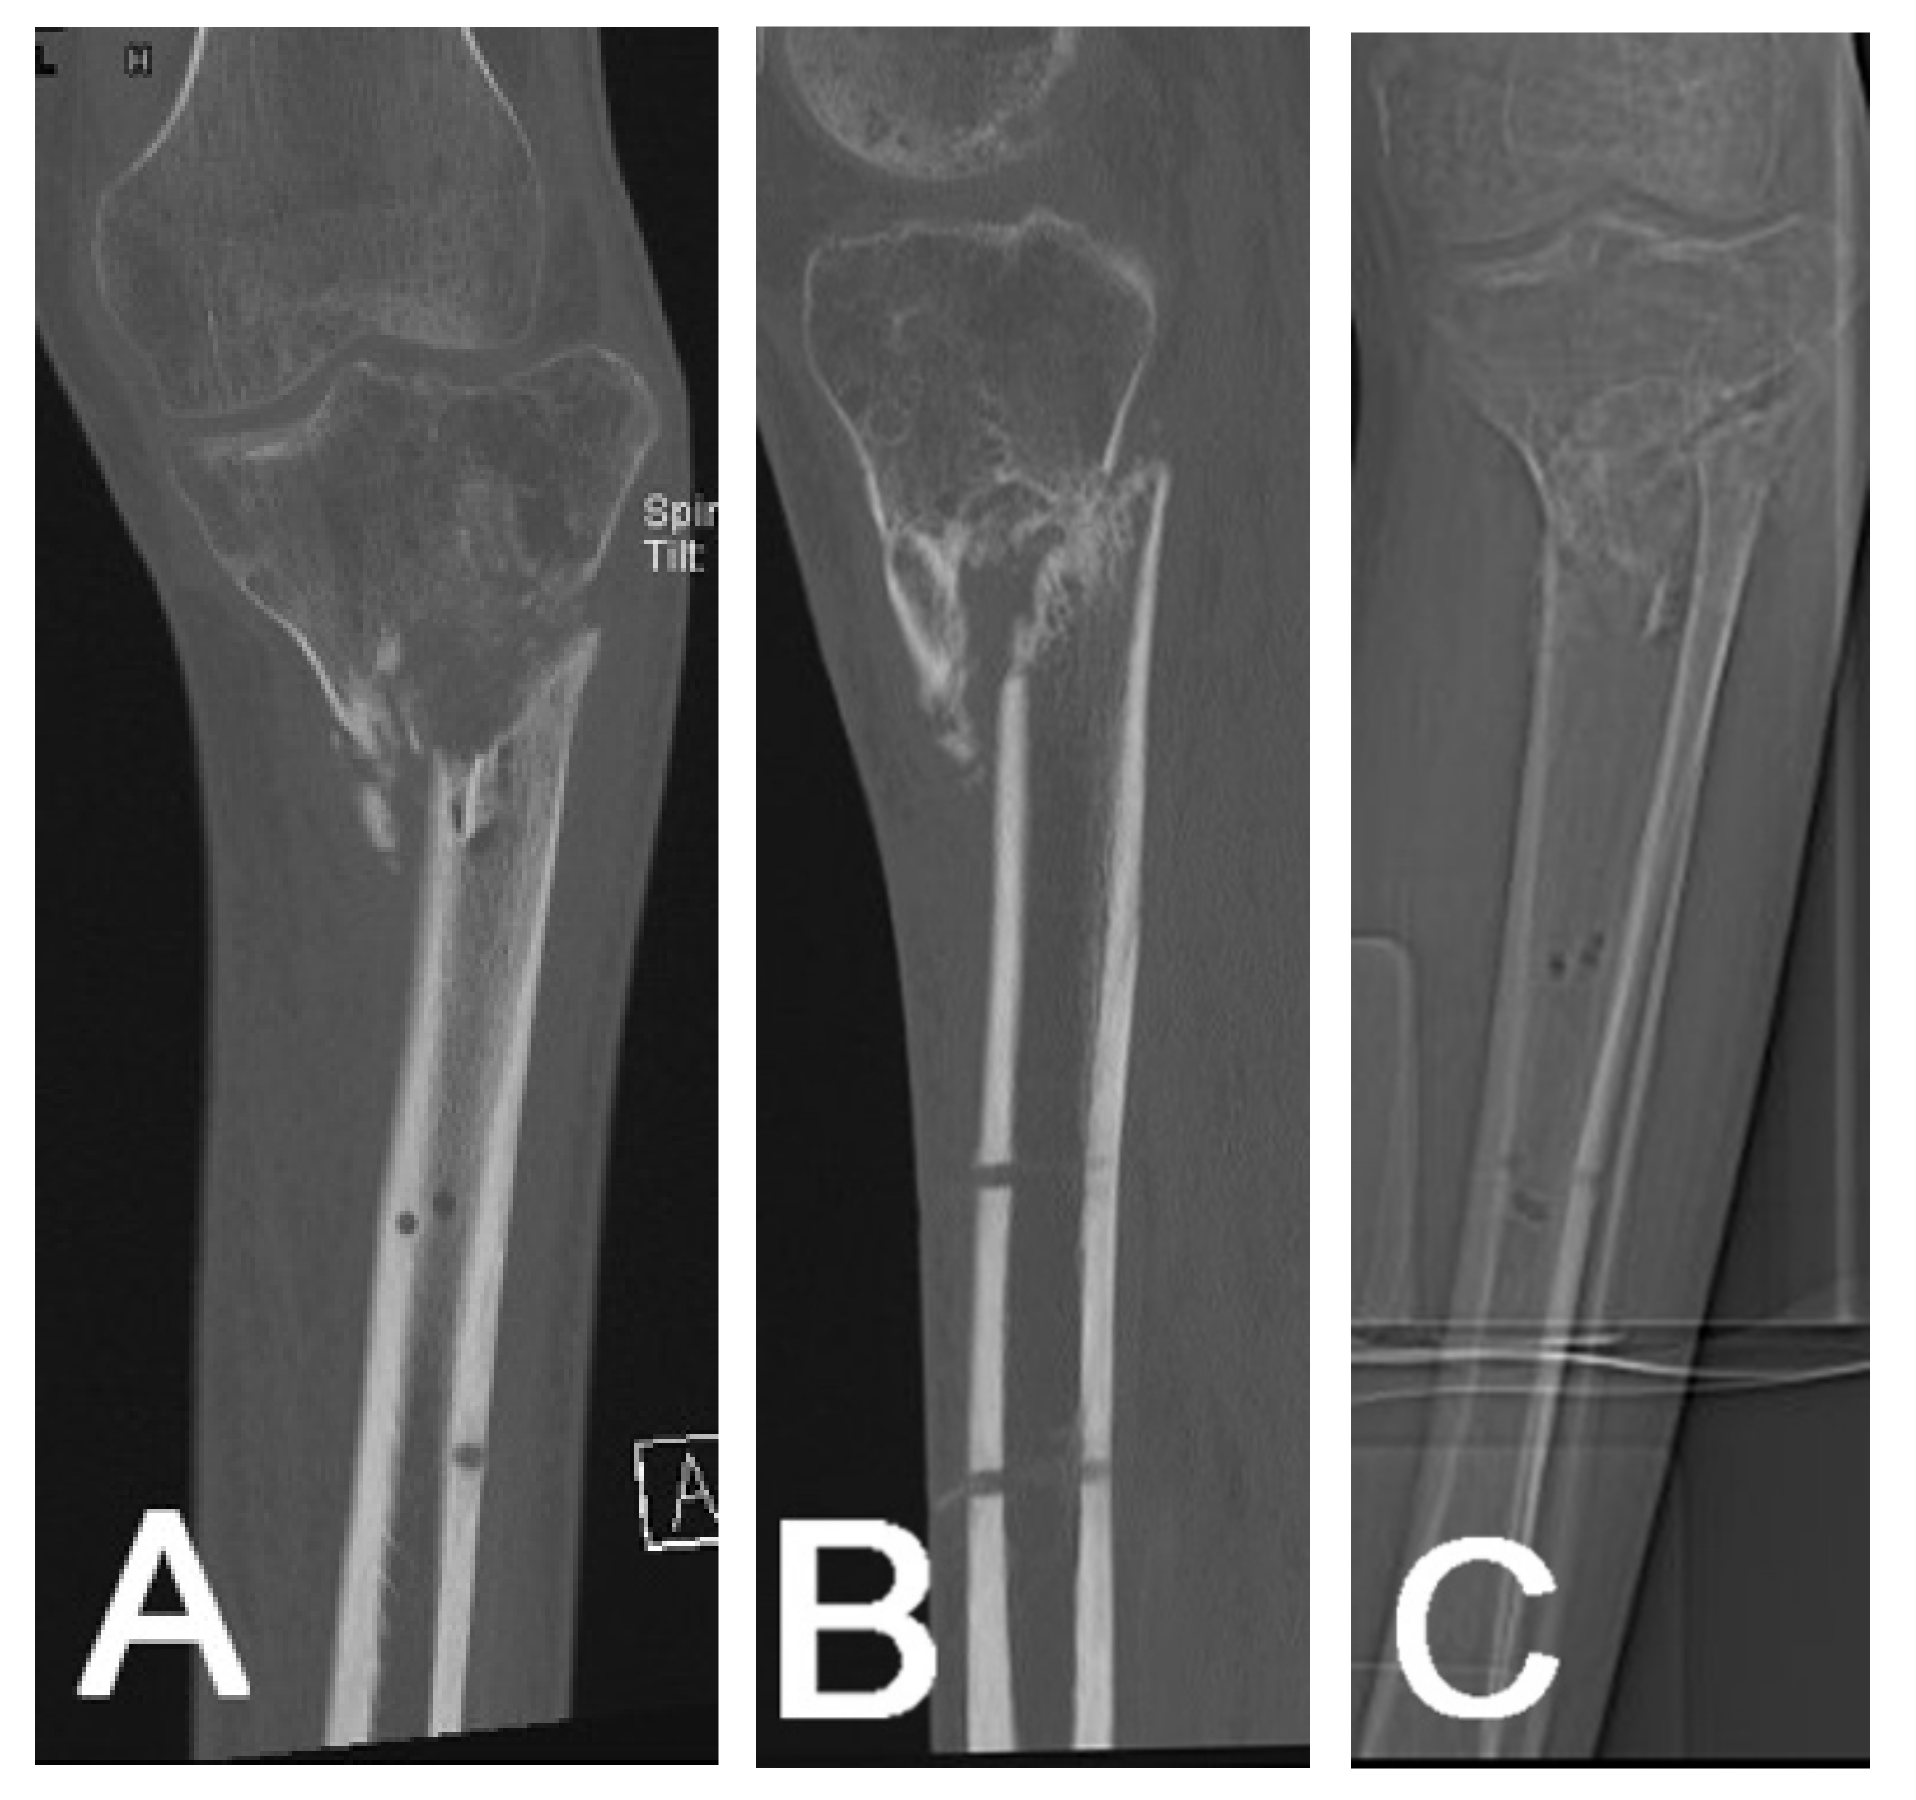

2.4.2. Non-Union Evaluation

2.4.4. Surgical Planning

2.4.5. Leg Length Measurement